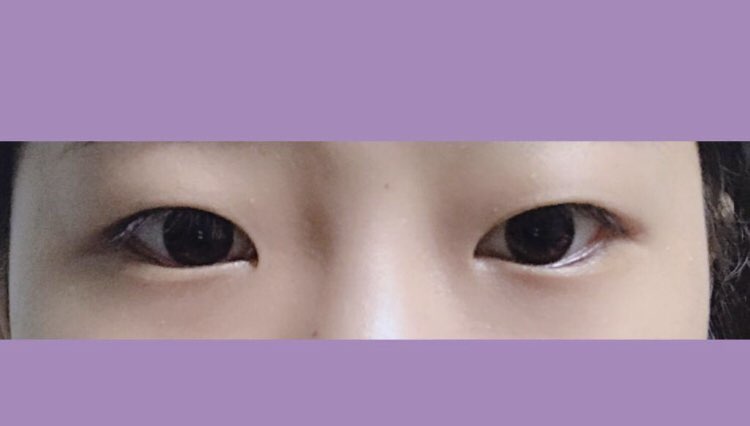

시각장애인을 위한 텍스트 정보 영역입니다.